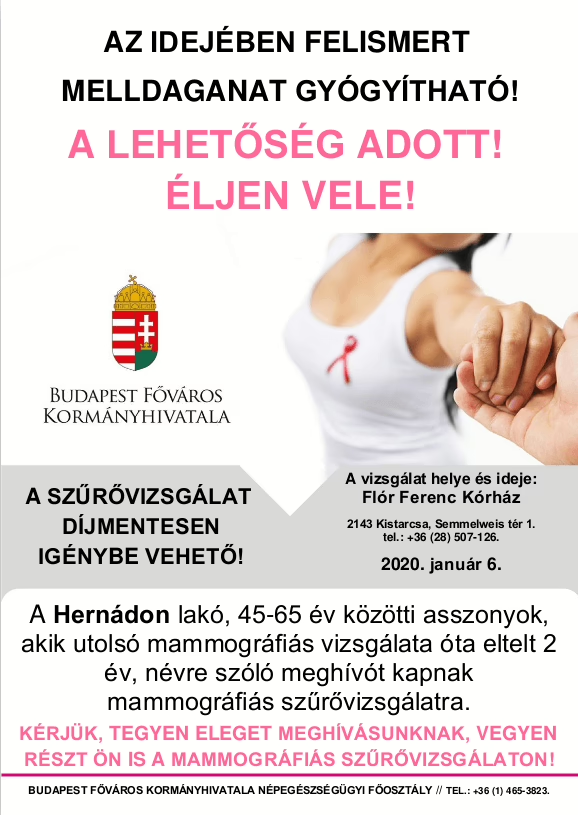

A Hernádon lakó, 45-65 év közötti asszonyok, akik utolsó mammográfiás vizsgálata óta eltelt 2 év, névre szóló meghívót kapnak mammográfiás szűrővizsgálatra.